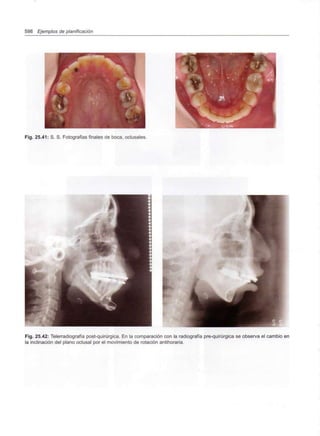

Capítulo 25 - Casos clínicos

553

555

557

571

575